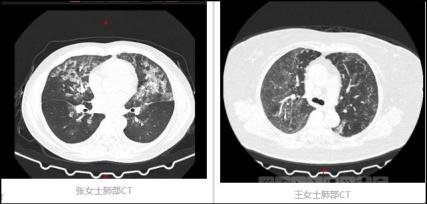

新冠肺炎ct图片影像,新冠肺炎ct影像

双肺多发毛玻璃样,正是新冠肺炎患者ct影像的典型特征.